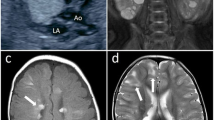

The case was a 25-year-old female PAH patient. No PAH history was reported in her family. She had dyspnea first at 12 years of age and dyspnea worsened gradually. She was diagnosed to have PAH at 18 years of age and estimated pulmonary arterial pressure was 60 mm Hg by echocardiogram and New York Heart Association functional class was II at diagnosis. After diagnosis, medical therapies such as bosentan, sildenafil and beraprost were administered. After 6 years of medical therapy (the timing of genetic analysis), mean pulmonary arterial pressure was 38 mm Hg and pulmonary vascular resistance 8.1 Wood units by right-sided heart catheterization, B-type natriuretic peptide was 14.7 pg ml−1 and New York Heart Association functional class was II. Figure 1 shows the chest X-ray and electrocardiogram. The genetic analysis of this patient was approved by the ethics committee of Kyorin University and written informed consent was obtained.